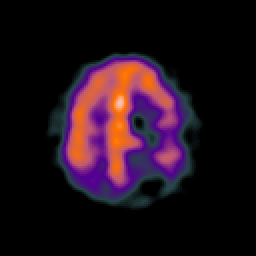

SPECT TC Study #1 -- Slice #39

[Home][Help][Clinical][Tour 1][Tour 2][Tour 3] Slice 39